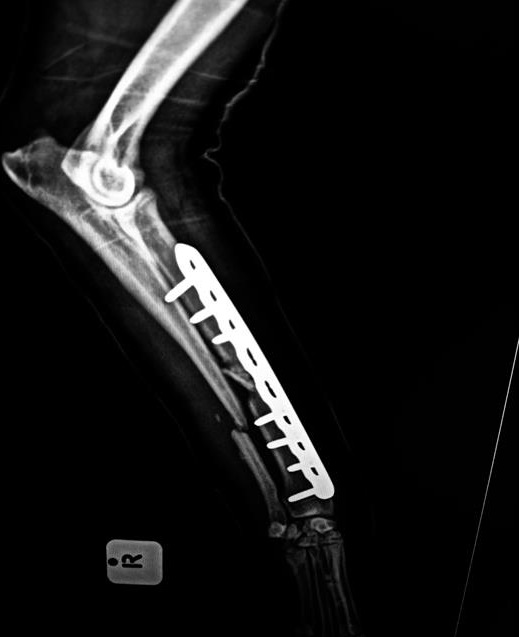

Die pen wat ingeplant is om Shiba se been te heg.

Met verdere ondersoek het dr. Emelia Crause gevind dat Shiba 'n spesialisoperasie sal moet ondergaan om sy been met metaalpenne te heg. Sy het Panorama genader vir hulp, maar Shiba se eienaars was nie finansieel in staat om vir die operasie te betaal nie - al het hulle dit teen helfte van die prys aangebied.

Odin se Marlene Mennie het dadelik vir Shiba na Eden Small Animal Hospital toe geneem waar X-strale 'n ernstige breuk aan Shiba se been bevestig het.

"Sy been was morsaf. Hy was in ontsettende pyn," sê Mennie.